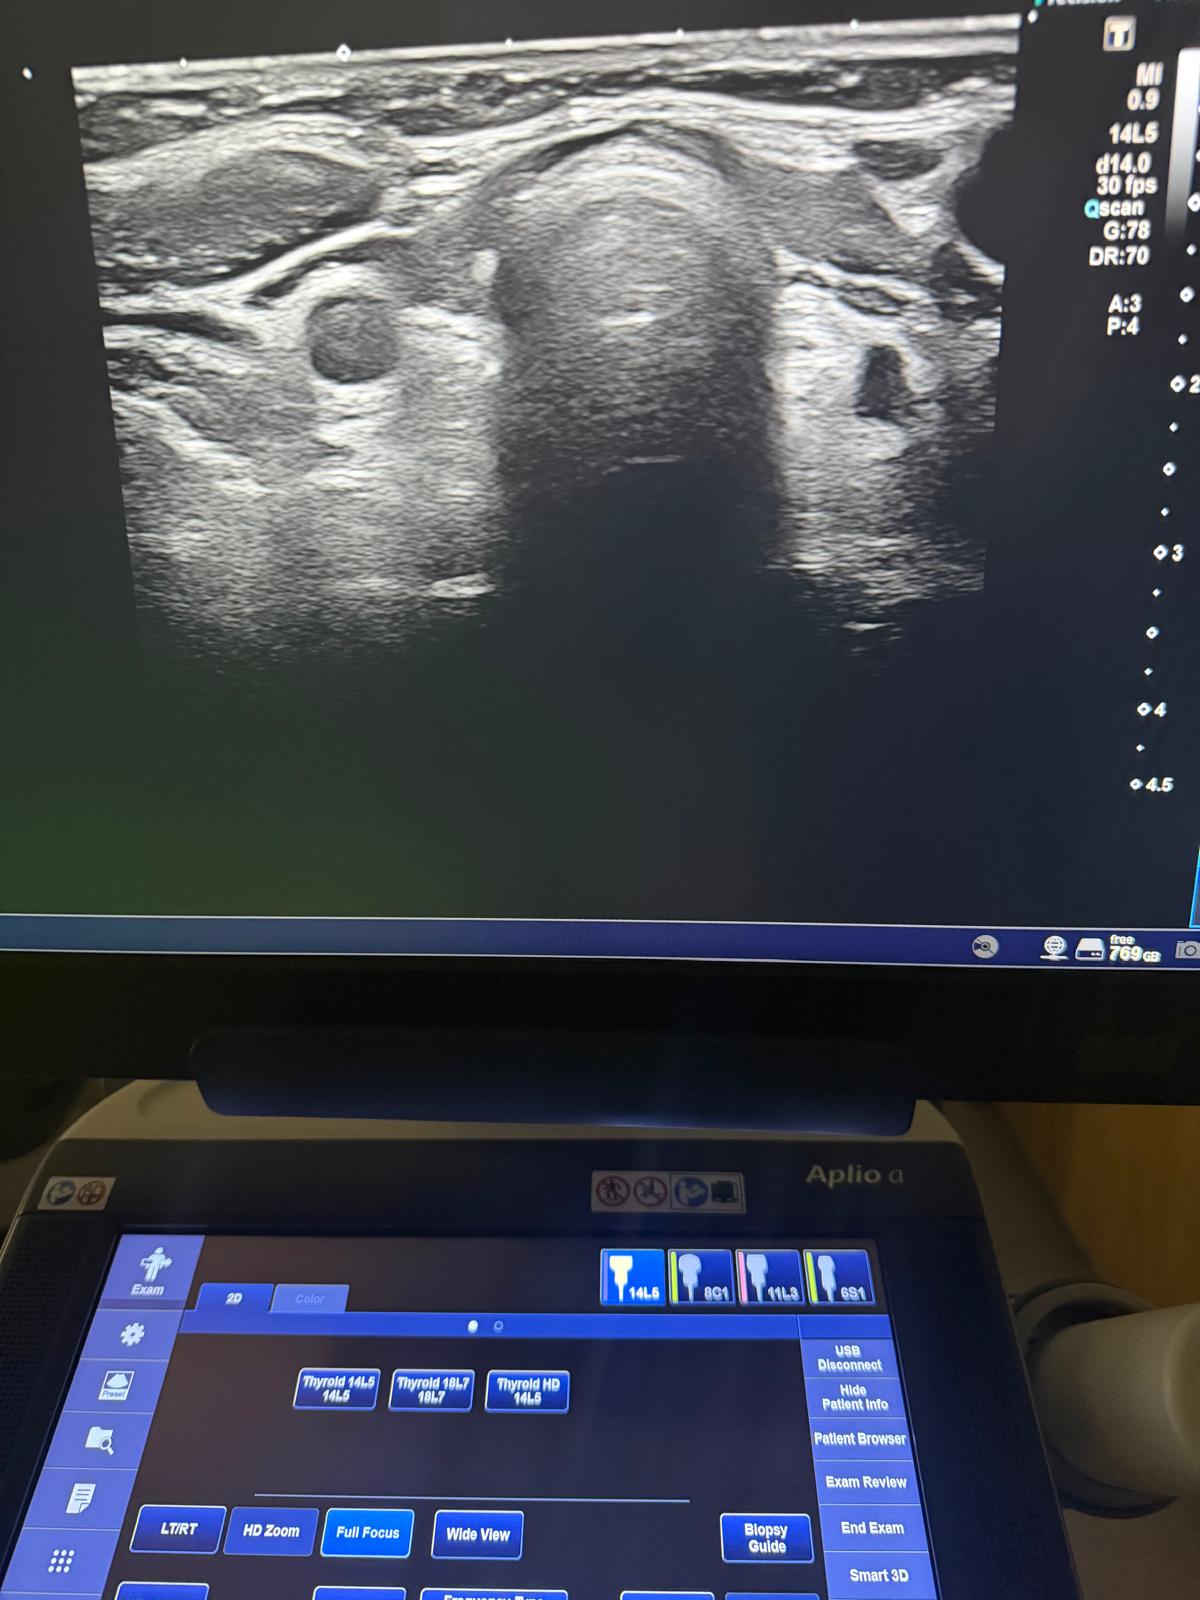

Vairogdziedzera ultrasonogrāfija

Vairogdziedzera ultrasonogrāfija ir izmeklējums, kas izmanto ultraskaņas viļņus, lai novērtētu dziedzera izmēru, struktūru un iespējamās patoloģiskas izmaiņas, piemēram, mezglus vai cistas.

Izmeklējumos tiek izmantota jaunākās paaudzes USG aparatūra, kas nodrošina precīzu un kvalitatīvu diagnostiku.